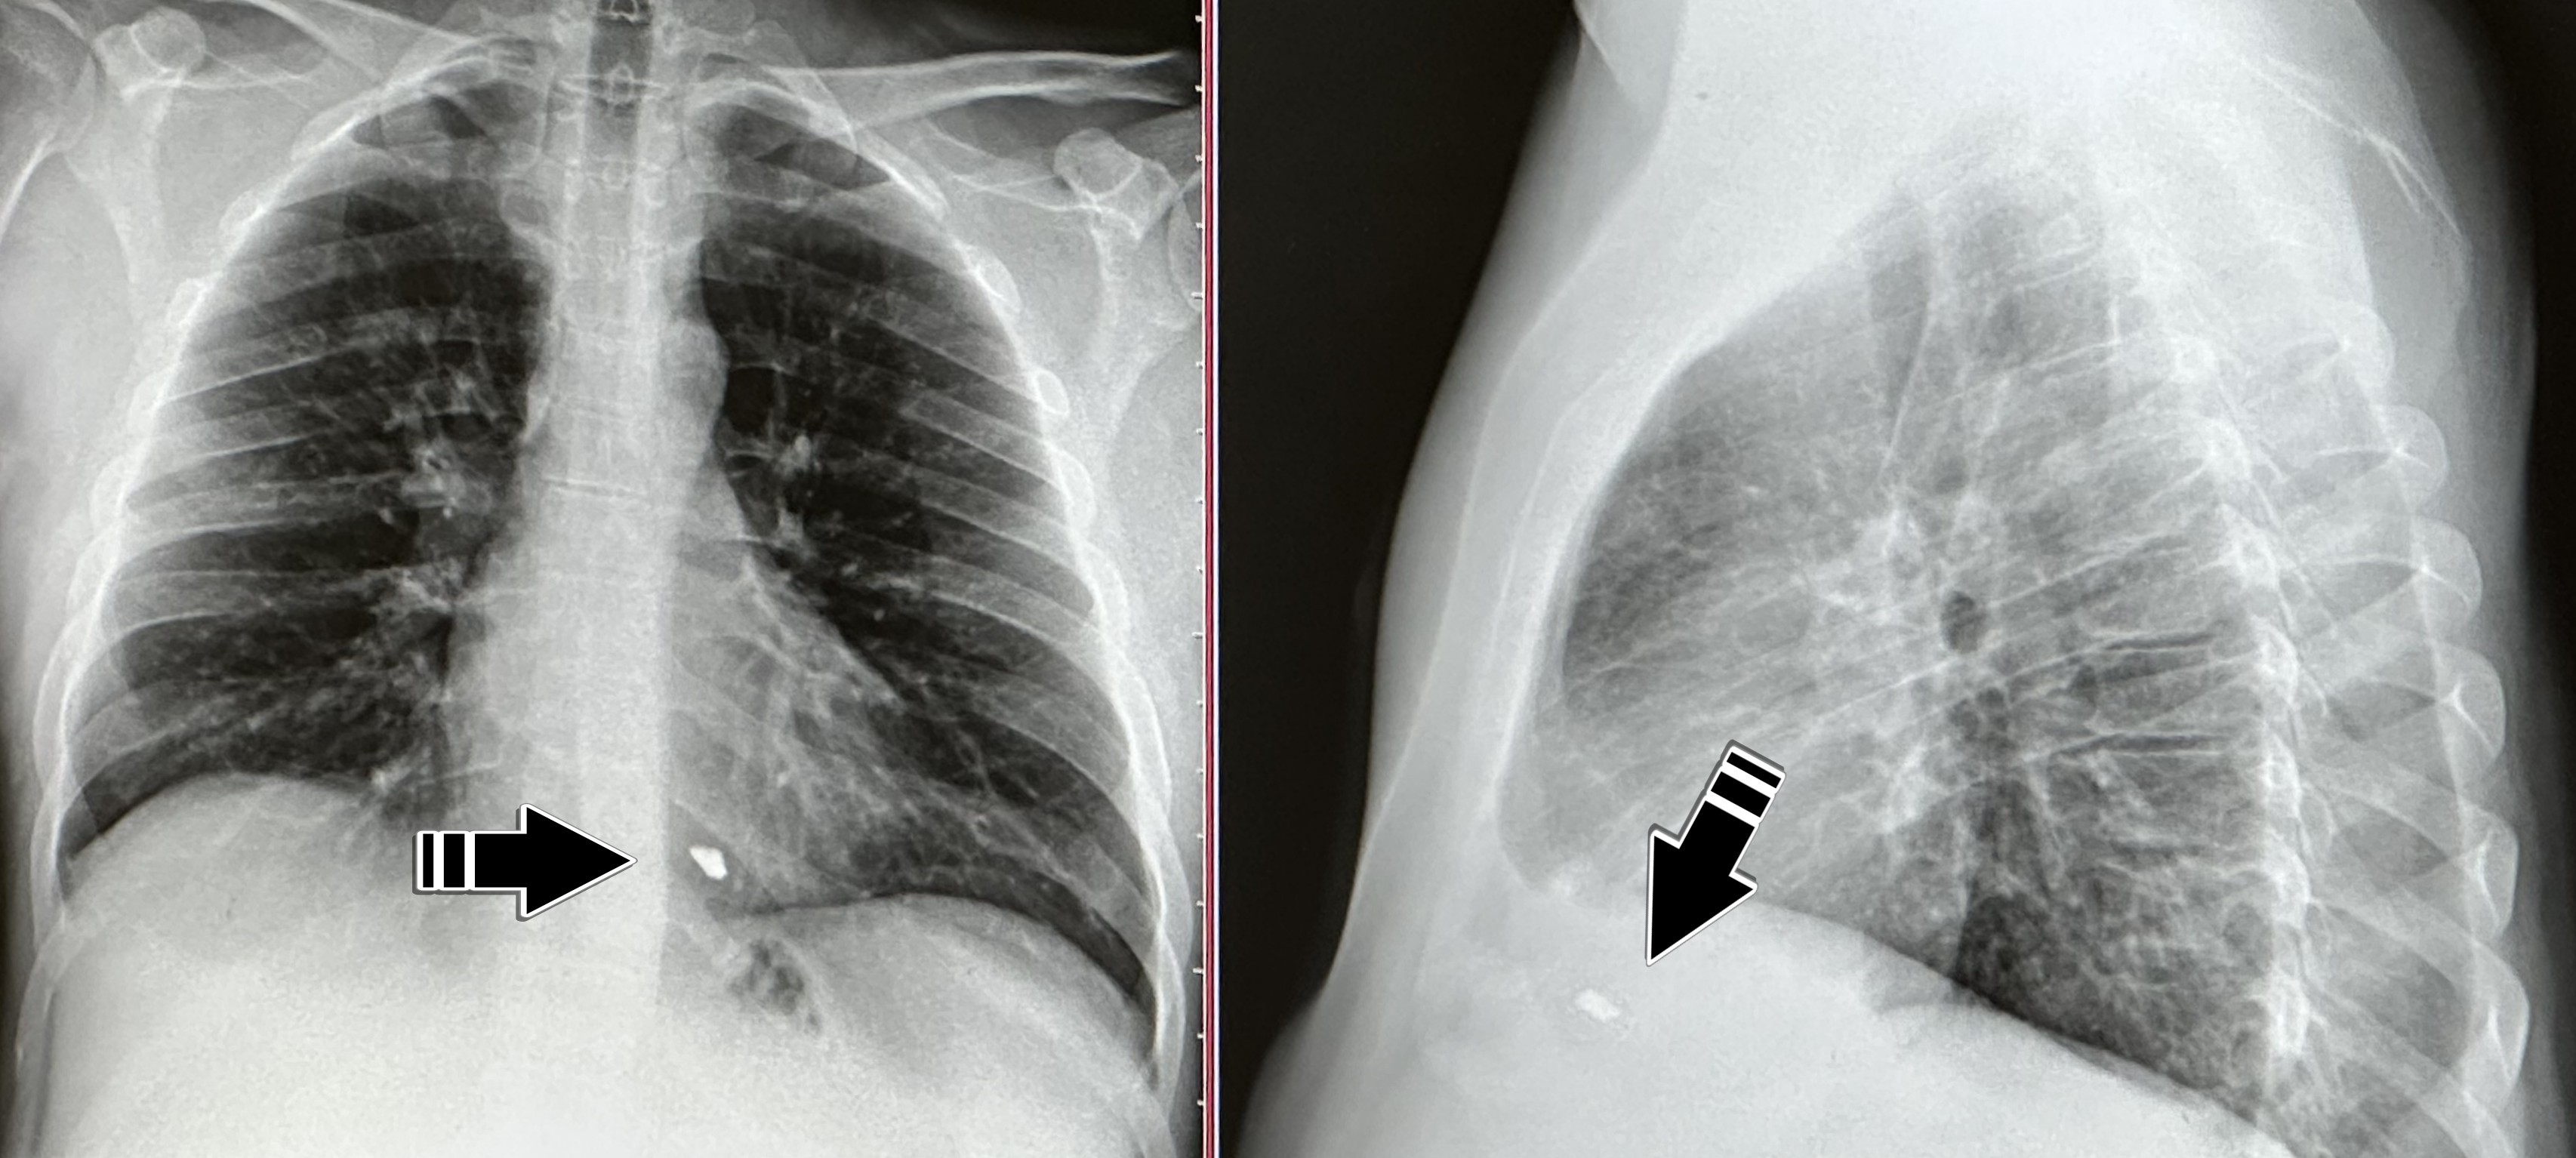

На снимке отчетливо видно светлую точку. Это осколок, который находится в правом желудочке